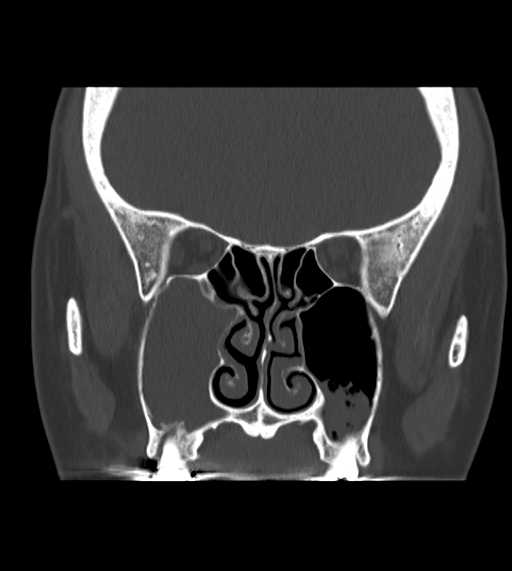

その他の領域

その他

副鼻腔炎